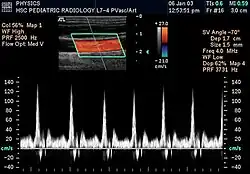

Потоковая спектральная доплерография (ПСД)

Импульсная ПСД